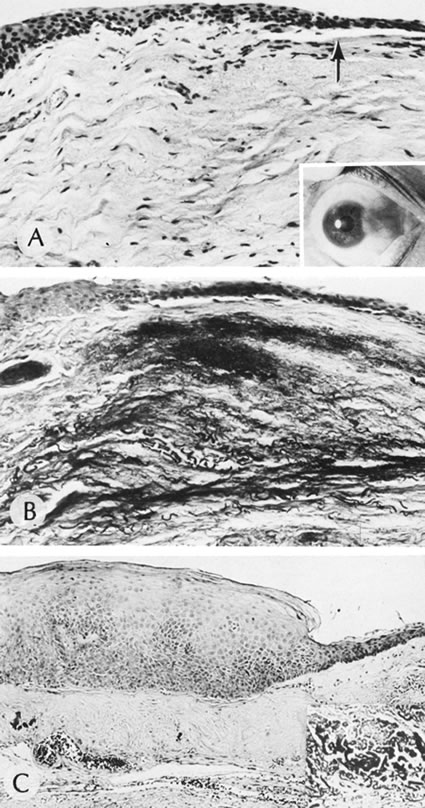

AXENFELD'S ANOMALY

Isolated Axenfeld's anomaly (posterior embryotoxon) consists of a clinically prominent Schwalbe's line (terminal end of Descemet's membrane) plus a variable number of iris processes extending from the peripheral iris to Schwalbe's line (Fig. 6). The condition is most likely a developmental arrest, late in gestation, of tissues derived from neural crest cells.66 The line appears as a deep linear opacity of the peripheral cornea of variable prominence and extent and is most often found temporally. The prevalence rate is approximately 15% to 25%.67,68 No race or sex predilection exists. Although the majority of the eyes are normal, an associated partial iris coloboma and other anomalies may occur.68 Axenfeld's anomaly may be associated with non-ocular abnormalities as part of Axenfeld-Rieger's syndrome (see later).

Fig. 6. Axenfeld's anomaly (posterior embryotoxin). A. The only abnormality visible from the 2-o'clock to 4-o'clock positions adjacent to the limbus is a “ropy” corneal opacity. The other eye is normal. B. A corneal opacity is present over 360 degrees near the limbus at the level of Descemet's membrane. C. Scanning electron micrograph shows the iris processes spanning the angle and attaching to the anteriorly displaced Schwalbe's ring. Artifactually broken ends of the iris processes are indicated by the arrows. D. Macroscopic appearance of the iris processes attaching to Schwalbe's ring. E. Iris processes attach to the anteriorly displaced Schwalbe's ring. (Courtesy of SEI Photoarchives.)

Histologically, Axenfeld's anomaly consists of dense collagen and ground substance covered by a monolayer of flattened endothelial or spindle-shaped cells at the terminal end of Descemet's membrane. The endothelium is contiguous with the endothelium covering the trabecular beams.68 Associated iris processes are composed of normal-appearing iris stroma.

RIEGER'S SYNDROME

Peripheral dysgenesis (isolated Rieger's syndrome) encompasses a wide spectrum of developmental abnormalities of anterior chamber angle tissues of neural crest origin associated with systemic anomalies.70 This group of abnormalities is important clinically because it is associated with an increased prevalence of glaucoma. The defects are thought to result from a developmental arrest in the third month of gestation. Rieger's syndrome probably includes those entities sometimes described as mesodermal dysgenesis and anterior chamber cleavage syndrome and most accurately called anterior segment dysgenesis.

Histopathologic changes are characterized by retention of primordial endothelial tissue on the iris and by anterior chamber angle and peripheral iris strands (Fig. 7). Continued contraction of component membranes causes progressive changes of the iris architecture. Glaucoma results from arrested development of the anterior chamber angle structures, characterized by incomplete maturation of the trabecular meshwork and Schlemm's canal and a high insertion of the peripheral iris.70

Fig. 7. Rieger's syndrome. A. Posterior embryotoxon, marked iridocorneal processes and iris hypoplasia are present. B and C. Arrows show the central location of Schwalbe's ring. (Courtesy of SEI Photoarchives.)